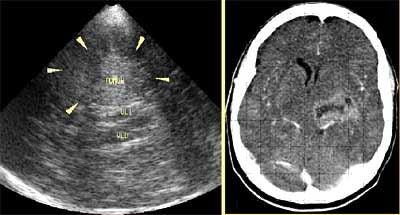

![]() |

| Dependiendo de la región a evaluar, la ecografía por Doppler transcraneano se realiza apoyando el transductor contra una de tres ventanas en la cabeza, incluyendo la ventana orbital (arriba), la ventana temporal (izquierda), y la ventana suboccipital (abajo). Imagen cortesía del Dr. Orlando Valls Pérez. |